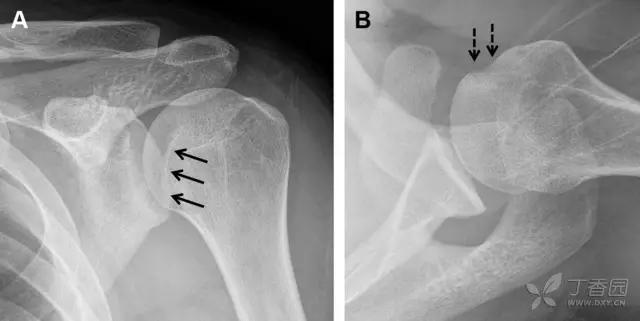

24 无移位的桡骨头/颈骨折

多发生于摔倒时,手掌撑地,受到轴向、外翻应力所致。常规的前后位片容易漏诊,常需加拍内斜位、外斜位、桡骨头-肱骨小头位片。后脂肪垫可见(位于鹰嘴窝内,一般不可见)和/或前脂肪垫抬高常提示骨性损伤。

图 2 桡骨头骨折。前后位(A)和侧位(B)片示后脂肪垫抬高(黑色箭头),前脂肪垫抬高(白色箭头),呈「帆船征」,其它表现正常;外斜位(C)和桡骨头–肱骨小头位(D)示桡骨头关节内骨折线(虚线黑箭头)累及桡骨颈(虚线白箭头)

29 Essex-Lopresti 损伤

Essex-Lopresti 损伤是桡骨头骨折伴有下尺桡关节脱位,导致骨间膜损伤,桡骨短缩。此种损伤,桡骨头骨折的诊断往往是明确的,容易忽视的是下尺桡关节脱位,特别是早期,下尺桡关节的症状不明显,X 线表示也不明显。

图 8 Essex-Lopresti 损伤。前后位(A)和侧位(B)示桡骨头关节内骨折(白色实线箭头);(C~E)伤后 1 个月复诊,患者诉腕关节疼痛,X 线(C,D)发现下尺桡关节脱位,(E)CT 进一步证实损伤的存在